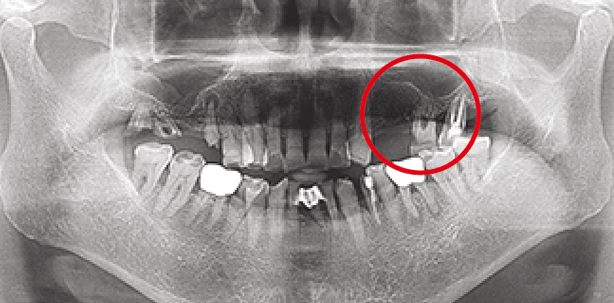

Fallbeschreibung

Der Patient stellte sich mit fehlenden Zähnen 24 und 25 und dem Wunsch einer implantatgetragenen Versorgung im seitlichen Oberkiefer vor. Die röntgenologische Diagnostik ergab einen sehr schmalen Kieferkamm in Regio 24 sowie ein ausgeprägtes Knochendefizit in Regio 26 und 27, sowohl im krestalen als auch im apikalen Aspekt. Abbildungen 1 bis 3 zeigen die signifikanten Knochendefekte Regio 24 bis 27.